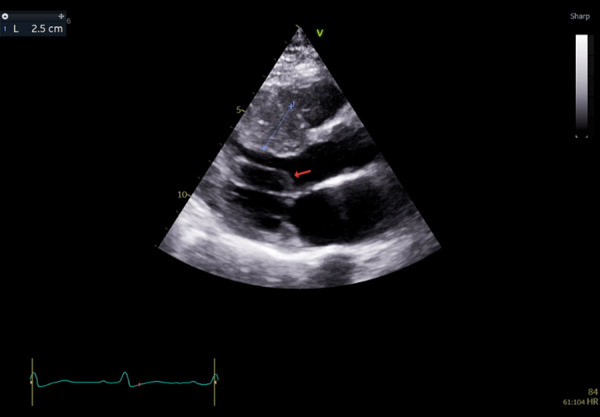

冠状动脉间通讯是一种罕见的先天性异常,定义为两条未闭冠状动脉之间的连接,于1972年首次被描述。我们报告的情况下,61岁的阿联酋女性谁提出了胸痛和心悸的急诊科,并与心脏疾病的强烈家族史。她最初被诊断为惰性肥厚性梗阻性心肌病并进行相应的治疗;然而,患者仍有症状。进一步的检查显示她的左旋冠状动脉(LCX)和左前降支冠状动脉(LAD)之间有冠状动脉间的通信。本病例强调了认识冠状动脉间通信对于HOCM患者更好预后的重要性,以及其潜在的临床意义,需要进一步研究以确定其真正意义。

Inter-coronary communication is a rare congenital anomaly, defined as a connection between two patent coronary arteries, and was first described in 1972. We report the case of a 61-year-old Emirati female who presented to the emergency department with chest pain and palpitations, along with a strong family history of cardiac disease. She was initially diagnosed with indolent hypertrophic obstructive cardiomyopathy and accordingly managed; however, the patient remained symptomatic. Further investigations revealed inter-coronary communication between her left circumflex (LCX) and left anterior descending (LAD) coronary arteries. This case highlights the importance of recognizing inter-coronary communications for better outcomes in patients with HOCM, as well as their potential clinical significance with the need for further studies to be done to pinpoint the true significance.